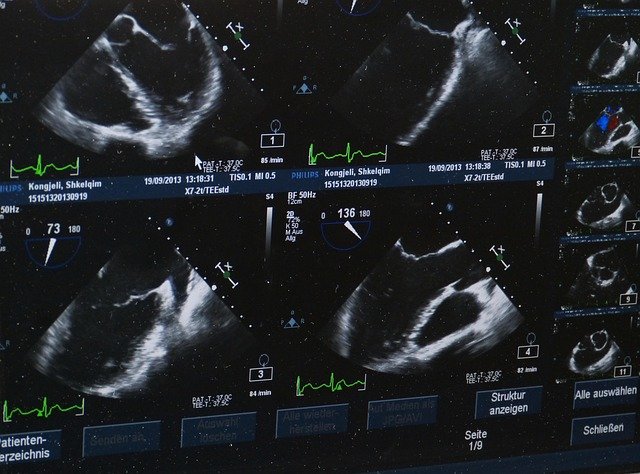

Comment lire une échographie ? Une échographie obstétricale est un procédé d’imagerie médicale qui utilise des ultrasons pour créer une représentation visuelle du fœtus et des organes reproducteurs de la mère. Cette technique non invasive procure des images en temps réel qui permettent de suivre le développement de votre bébé sans aucun risque. Les centres comme EchoFamille ou FuturEcho proposent souvent des échographies à différents stades de la grossesse, afin de garantir un suivi précis.

Au cours des examens, plusieurs aspects du fœtus sont évalués : la croissance, la morphologie, la fréquence cardiaque, ainsi que la position du placenta. Par exemple, BabyScan utilise une technologie de pointe pour une meilleure définition des images, rendant les détails plus distincts et rassurants pour les parents. De plus, l’âge gestationnel peut être déterminé avec précision grâce à des mesures spécifiques comme la longueur cranio-caudale.

La fréquence cardiaque fœtale, par exemple, est un indicateur principal. Elle doit être régulièrement mesurée pour s’assurer que le cœur de bébé bat dans la norme. Cette donnée est souvent affichée en haut ou en bas de l’écran sous la forme d’une courbe ou d’un chiffre précis. EchoBien-être insiste sur l’importance de ce paramètre surtout lors du premier trimestre.